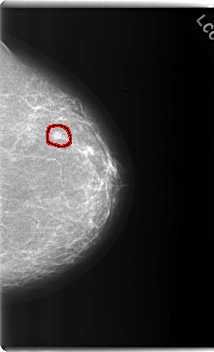

C_0187_1.LEFT_MLO

FILE: C_0187_1.LEFT_CC.OVERLAY

TOTAL_ABNORMALITIES 1

ABNORMALITY 1

LESION_TYPE MASS SHAPE ROUND MARGINS SPICULATED

ASSESSMENT 5

SUBTLETY 5

PATHOLOGY MALIGNANT

TOTAL_OUTLINES 1

BOUNDARY